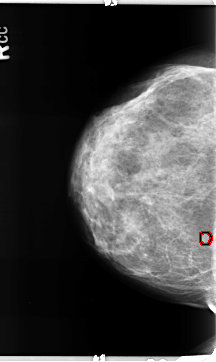

B_3157_1.RIGHT_CC

RIGHT_CC LINES 4704 PIXELS_PER_LINE 2800 BITS_PER_PIXEL 12 RESOLUTION 50 OVERLAY

FILE: B_3157_1.RIGHT_CC.OVERLAY

TOTAL_ABNORMALITIES 1

ABNORMALITY 1

LESION_TYPE MASS SHAPE LOBULATED MARGINS CIRCUMSCRIBED

ASSESSMENT 4

SUBTLETY 4

PATHOLOGY BENIGN

TOTAL_OUTLINES 1

BOUNDARY